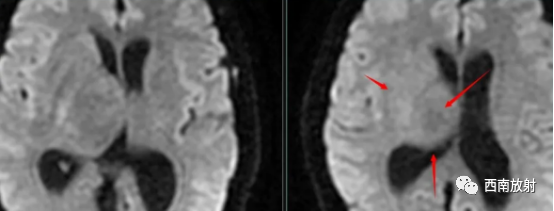

中枢神经系统淋巴瘤主要发生在脑内深部白质,病灶大多位于幕上。多数病灶邻近脑室。病灶形态多为团块状,较典型表现如同“握拳”者。位于胼胝体压部的病灶沿纤维构形,形似蝴蝶,颇具特征。该病“瘤周水肿”在T2WI呈高信号,不仅反映该部位脑组织水分增加,还有肿瘤细胞沿血管周围间隙浸润、播散的因素;另一特征为“瘤周水肿”与肿瘤体积不一致。本病大多数肿瘤体积相对较大,具有较明显占位效应,但周边水肿相对轻微。非免疫功能低下者发生淋巴瘤时,瘤体内囊变、坏死少见。本病也可发生在中枢神经系统的其他部位,脑外受累部位有颅骨、颅底、脊髓等。

▲病例:脑淋巴瘤。脑深部结节病灶,具有刀切征、凹陷征或肚脐凹征、尖角、多发。DWI呈稍高信号,形态上怪异,波普NAA及Cho减低,出现导致LL峰。颈部、胸廓入口区及腋窝多发淋巴结肿大并相互融合。